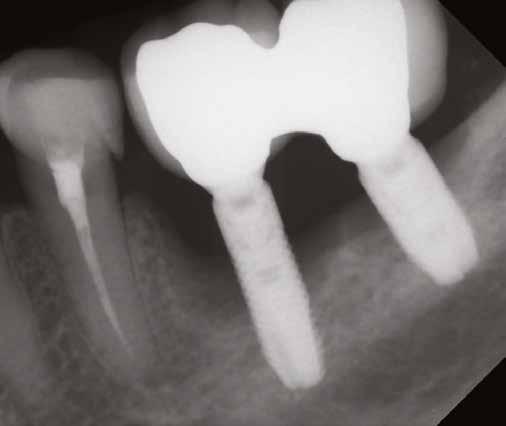

1. a–d. ábra: Műtét előtti állapot mind a négy páciensnél. 1. eset (a). 2. eset (b). 3. eset (c). 4. eset (d).

digitális implantátumtervezés követett (SICAT és Sidexis, mindkettő Dentsply Sirona; 1. ábra).

3. a–b ábra: Röntgenfelvételek három hónap után (a) és a gyógyulási csavarok behelyezve (b, 1. eset).